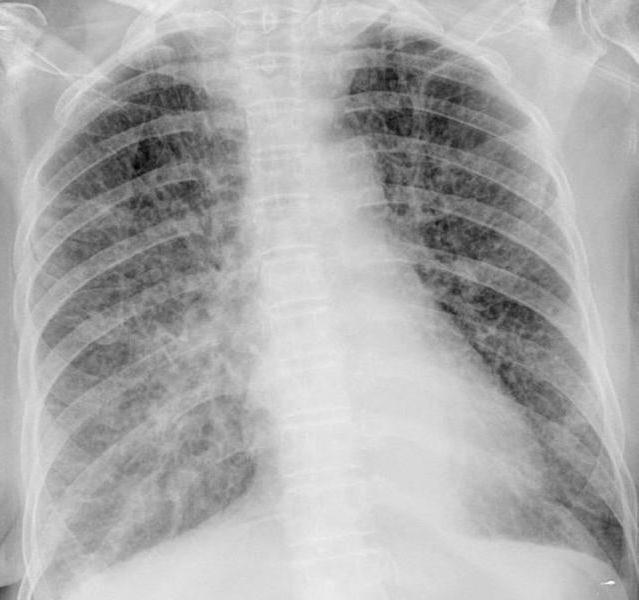

Точно определить вирусную пневмонию и назначить правильное лечение может только врач. Он изучает эпидемиологическую обстановку и анамнез. Далее необходимо будет сдать общий анализ крови и пройти рентгенологическое обследование.

При наличии пневмонии на рентгенологическом снимке можно увидеть в нижней доле лёгких мелкоочаговые тени и усиление интерстициального рисунка. Кроме того, специалист изучает промывные воды бронхов и мокроту.

Врач изучает все анализы и исключает другие болезни, имеющие похожие признаки. После этого он обозначает тип вируса, который вызвал данный недуг.